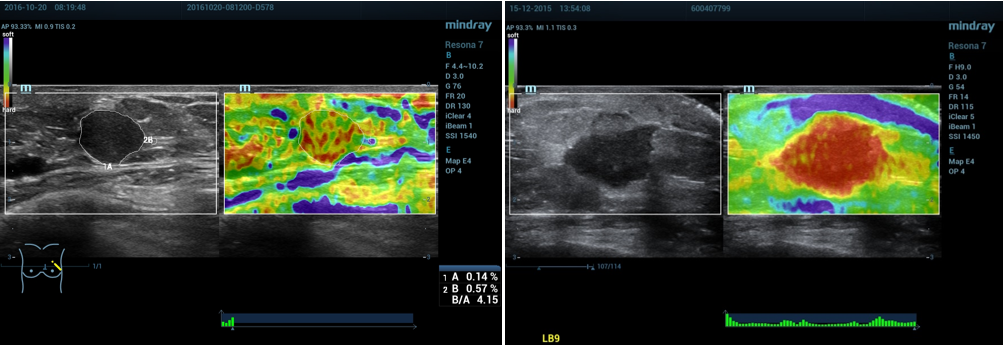

3、数据测量:

①按Measure,选择测量应变比(描记法)。

②分别描记“肿块区域A”和“腺体或脂肪组织”的蓝色区域B,系统自动计算出应变比B/A。

③通过触摸屏shell下的按钮调节Shell大小为2mm(此为多中心研究的诊断标准)。

④系统自动计算出肿块周边区域Shell的应变比B/Shell。

4、正确示范:

(1)乳腺应变式弹性成像(脂肪层出现蓝色带):